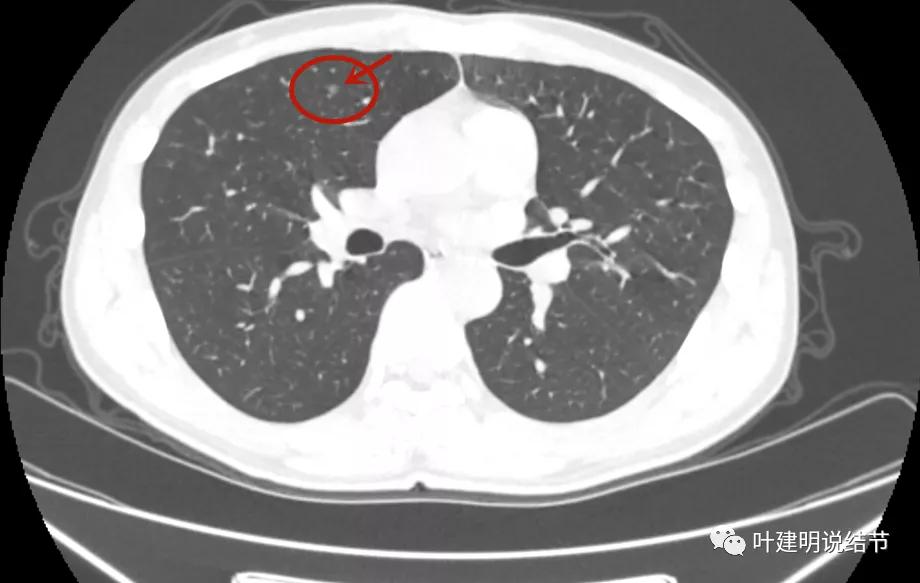

病灶3:右上叶前段微小淡磨玻璃结节,甚小,2-3毫米许,影像特征不明显,轮廓较清。

但可惜当时不是薄层扫描的。后来口服莫西沙星6天,并于2021年11月复查的是薄层的:

病灶1几乎没什么变化,实性部分范围感觉略大,显模糊。我考虑是因为薄层的关系,不是病灶有明显变化,轮廓仍是不清的

病灶3较前感觉明显了点,但我仍考虑也是扫描条件不同的关系,不能认为是进展。